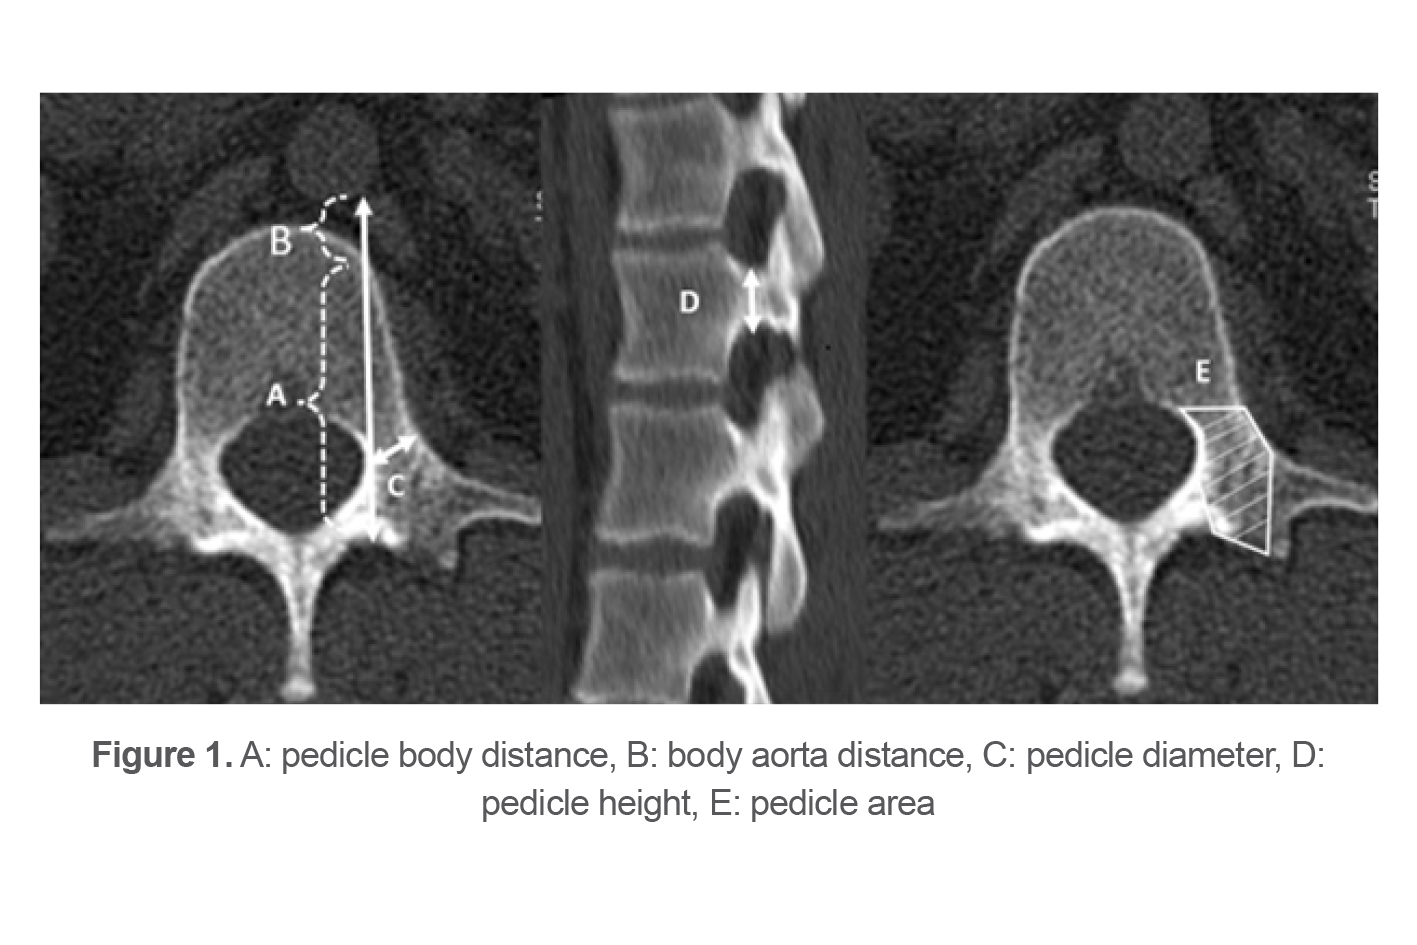

Demographic information of the subjects, including age, sex, trauma mechanism, and Body Mass Index (BMI), was collected. The distance between the pedicle (screw entry point) and aorta (pedicle body distance) (Figure 1A), anterior vertebral body and aorta body aorta distance (Figure 1B), sum of pedicle body distance and body aorta distance diameter (Figure 1C), height (Figure 1D), and area pedicles (Figure 1E), were measured through MARCO PACS (METRIC V10.1) software scale.

Figure 1. A: pedicle body distance, B: body aorta distance, C: pedicle diameter, D: pedicle height, E: pedicle area